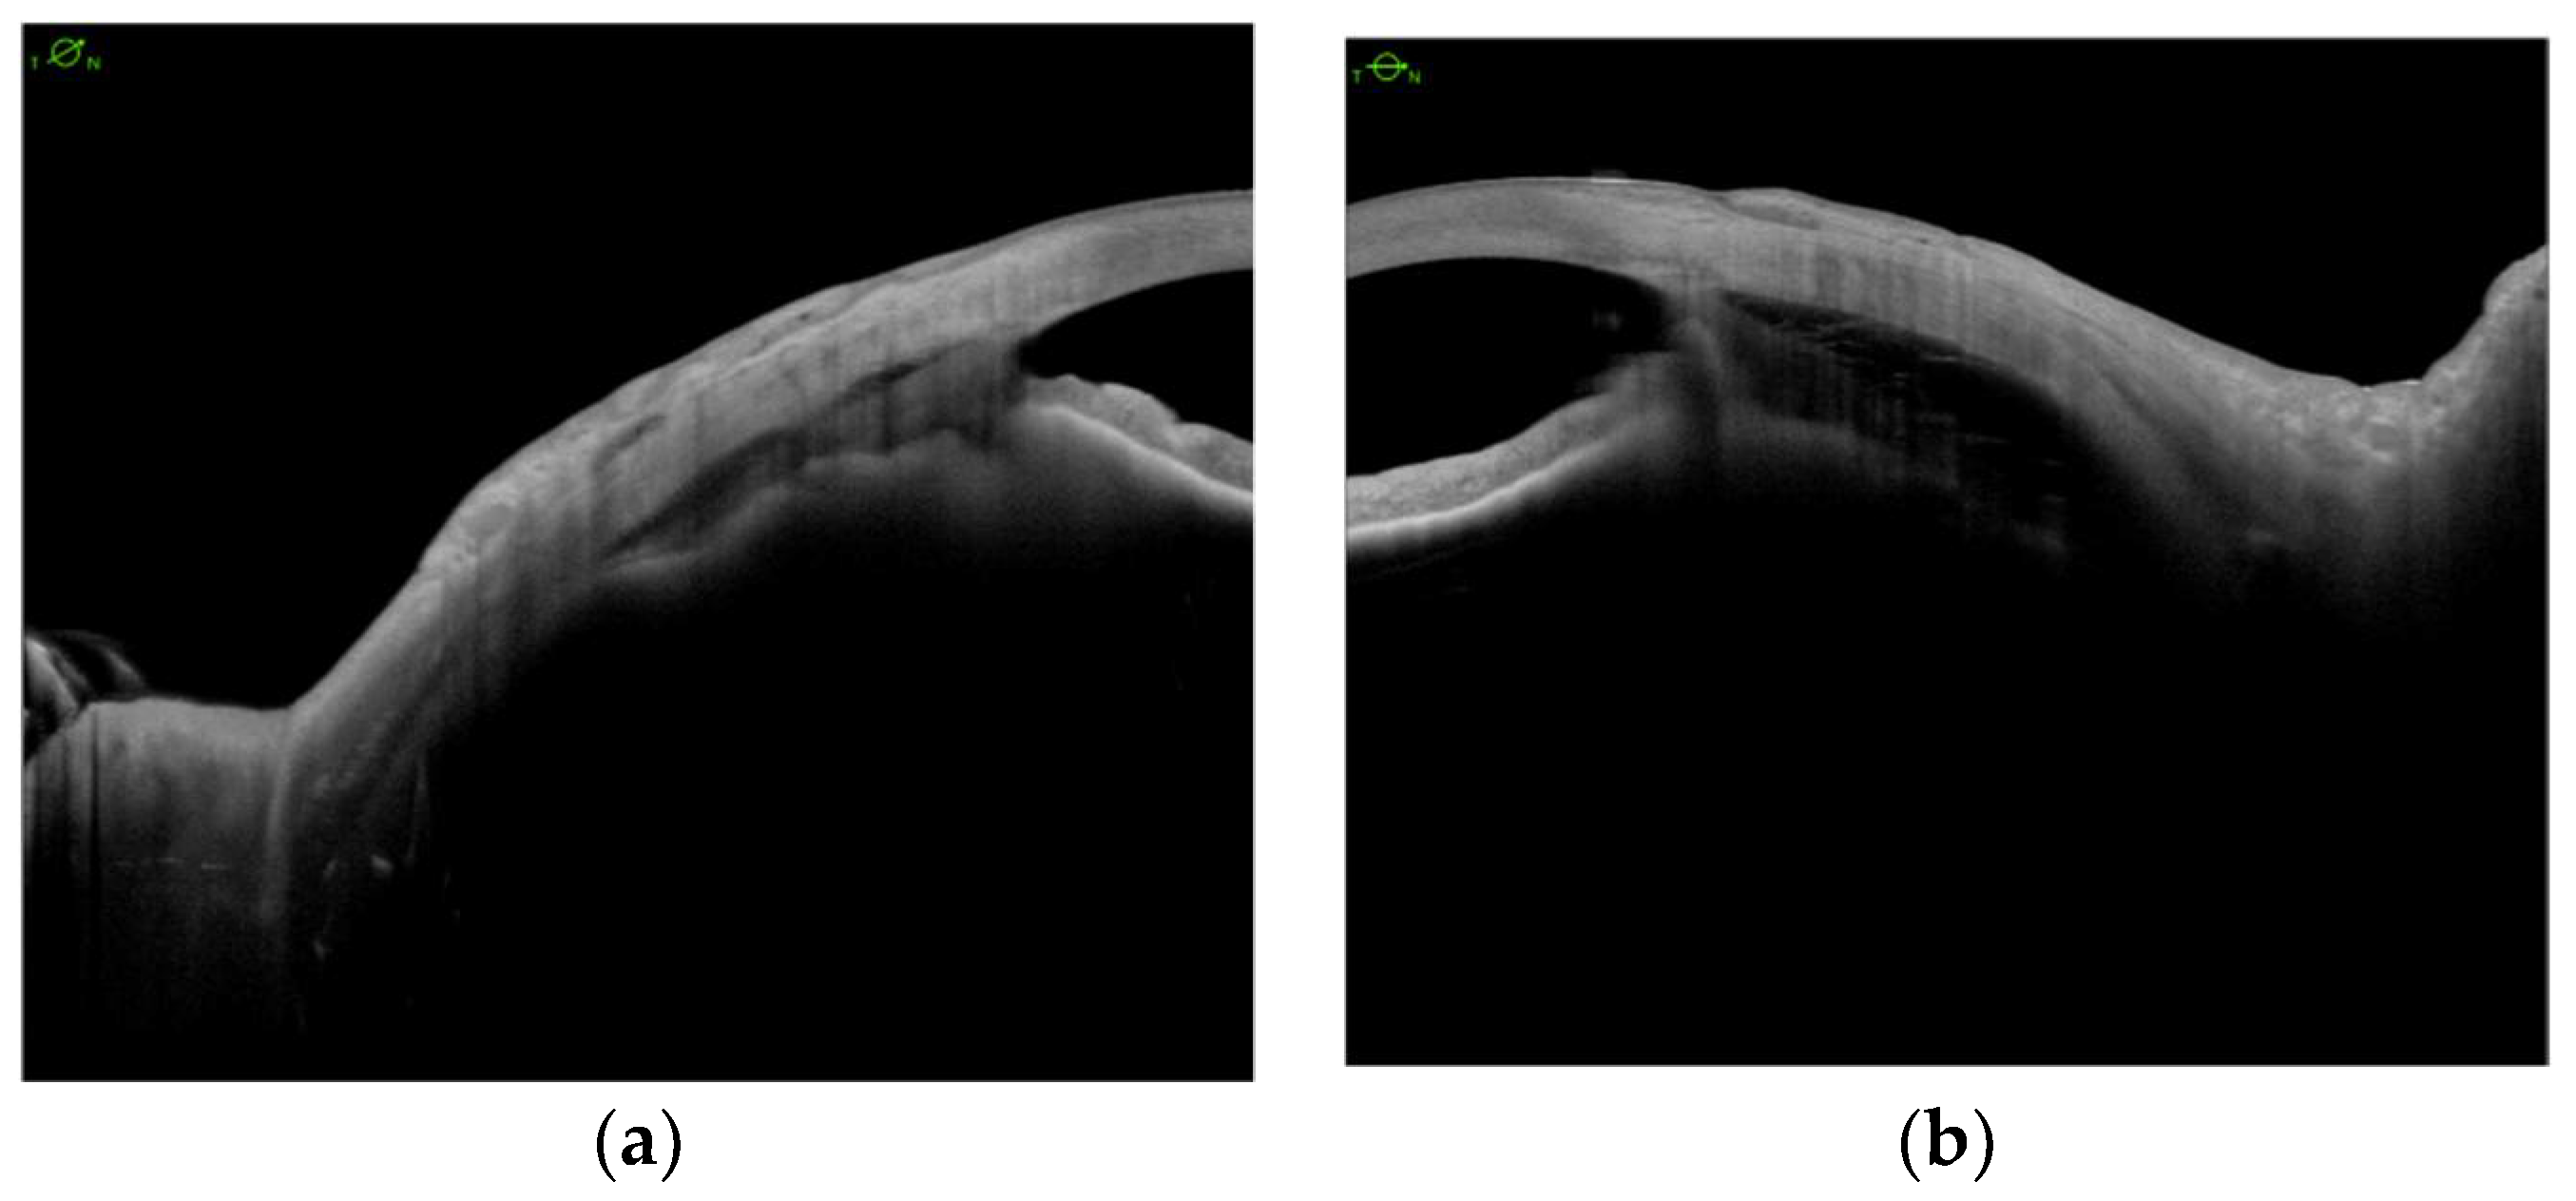

Encircling Scleral Buckling Surgery for Severe Hypotony with Ciliary Body Detachment on Anterior Segment Swept-Source Optical Coherence Tomography: A Case Series

2. Materials and Methods